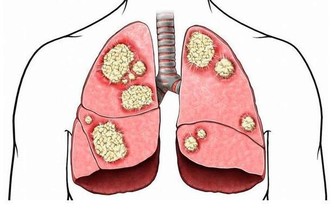

當人的年齡增大後,關節潤滑液會越來越少,潤滑度不夠,關節必定會出現磨損,這時候就會出現關節炎、骨刺、骨質疏鬆等疾病。

嚴重的甚至會導致骨關節壞死,這種屬於病理性關節響,一般伴隨著疼痛、活動受限,或者關節突然卡住。